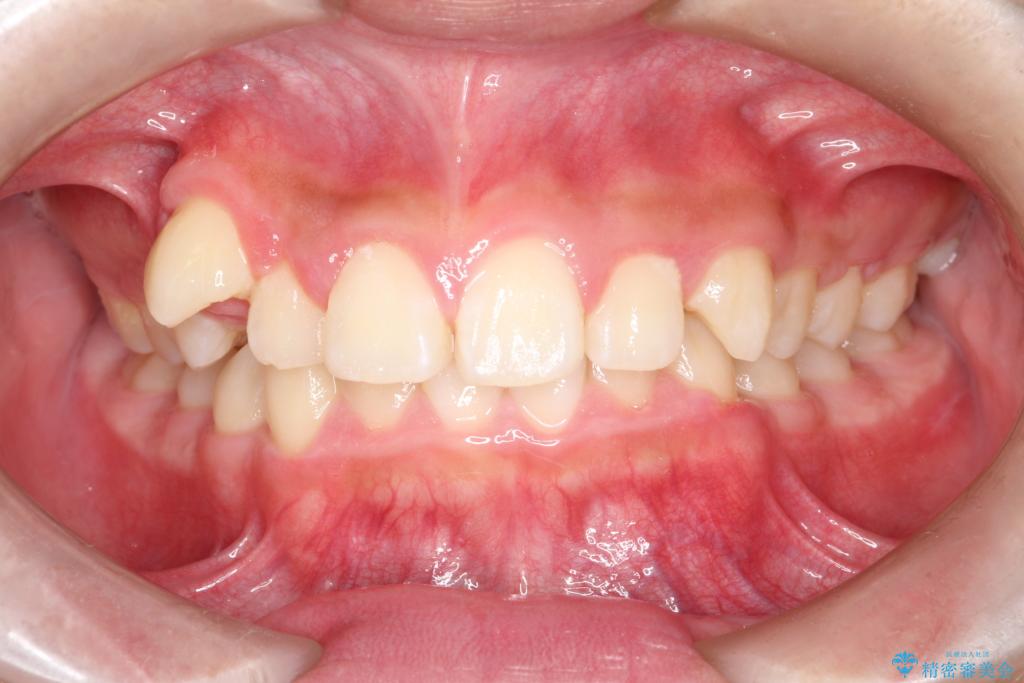

- 八重歯と咬み合わせを治したいを主訴にご来院された患者様です。

矯正の精密検査の結果上顎左右4番の計2本を抜歯し、審美性に配慮したワイヤー矯正装置(審美装置)を用いて治療を行いました。

八重歯などの歯列のデコボコが綺麗に改善され、患者様にも大変喜んでいただけました。また、咬み合わせが深い「ディープバイト」も併せて改善し、見た目だけでなく機能面でもバランスの取れた咬合を獲得しています。